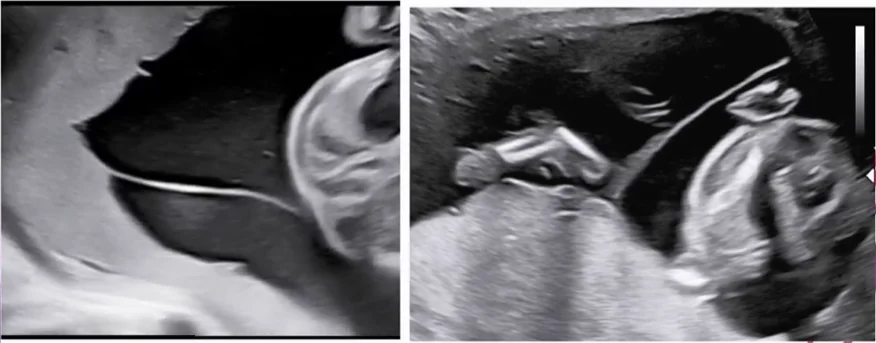

Dây rốn quấn nhau ở song thai (Cord entanglement)